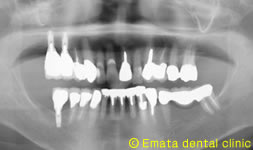

After

上顎洞挙上術(ソケットリフト)をおこないインプラントを埋入しました。

上顎洞の位置が低いためにインプラントが困難な方にもこの手術を併用することでインプラントが可能となります。